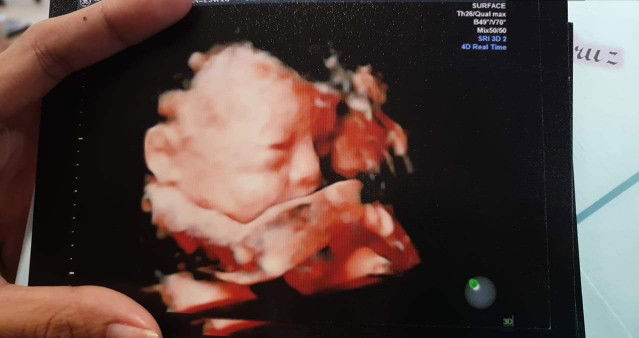

Share 3D ULTRASOUND

hello mga momshie ... 25weeks 2days Preggy Name please po Baby Boy ? Last Name LEE